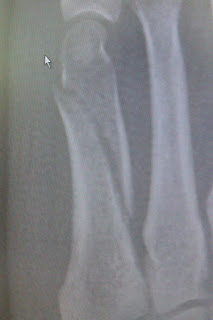

Toe fracture and metatarsal fracture. Metatarsal healing broken 5th

Metatarsal fractures. Toe fracture metatarsal 5th foot relocation office

Foot sprain. Healing of a broken 5th metatarsal. Spiral fracture fifth metatarsal shaft